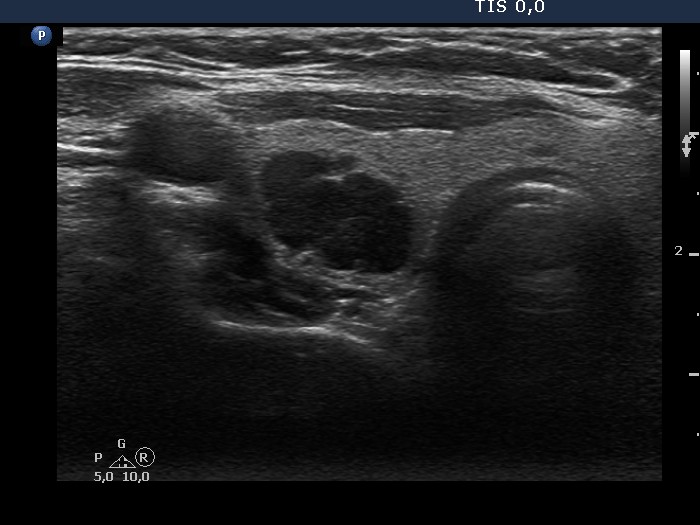

Halo sign and vascular pattern of nodules - case conp 068

Follow-up investigation seven years later (ultrasonographic picture 4)

Middle part of the right lobe, transverse scan. There is a deeply hypoechoic lesion which proved to be a parathyroid adenoma on histopathology.